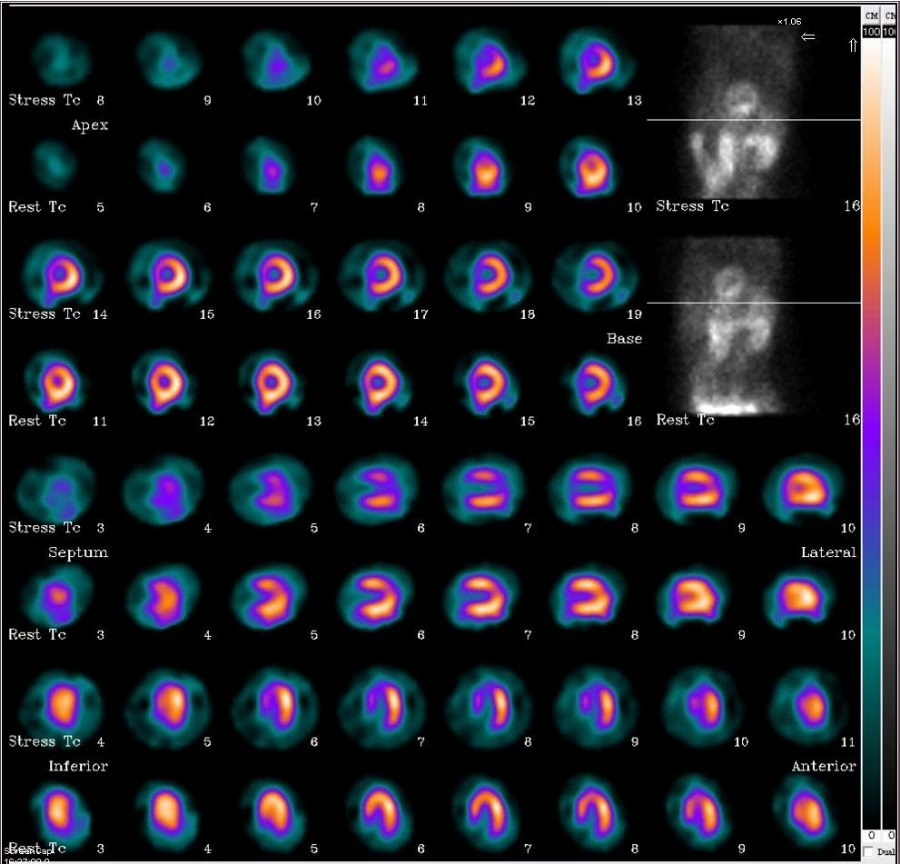

Cintilografia do Miocárdio

Este é um dos exames mais comuns e cruciais da medicina nuclear. A cintilografia do miocárdio ajuda a visualizar indiretamente o fluxo sanguíneo que alimenta o principal músculo do coração, o ventrículo esquerdo, responsável por impulsionar o sangue para todo o corpo. Ela é indicada para:

- Diagnosticar e prevenir a isquemia miocárdica (falta de aporte sanguíneo ao coração).

- Avaliar pacientes com fatores de risco para doenças cardíacas, como diabetes, hipertensão, colesterol elevado, sobrepeso e histórico familiar.

- Monitorar pacientes que já realizaram outros procedimentos cardíacos, como cateterismo, angioplastia ou cirurgia de revascularização.

O exame de cintilografia do miocárdio é feito em duas fases:

- Fase de Repouso: O paciente recebe o radiofármaco por via intravenosa. As imagens do fluxo sanguíneo são coletadas após 30 a 60 minutos.

- Fase de Estresse ou Esforço: Após a fase de repouso, uma nova injeção do radiofármaco é realizada, desta vez durante um teste ergométrico (teste de esforço físico). Para pacientes que não podem realizar esforço físico, utiliza-se o estresse farmacológico, com medicamentos como dipiridamol ou dobutamina, que aumentam o fluxo sanguíneo nas artérias coronárias, simulando o esforço.

Ambos os métodos são essenciais para comparar o fluxo sanguíneo do coração em diferentes condições, auxiliando o médico na identificação de áreas com problemas.

Para a cintilografia do miocárdio, que é um dos exames mais complexos, a duração total, contemplando as duas etapas (repouso e estresse), pode variar de quatro a seis horas. As imagens finais, por sua vez, são geralmente obtidas entre 15 e 60 minutos após a conclusão das duas fases.